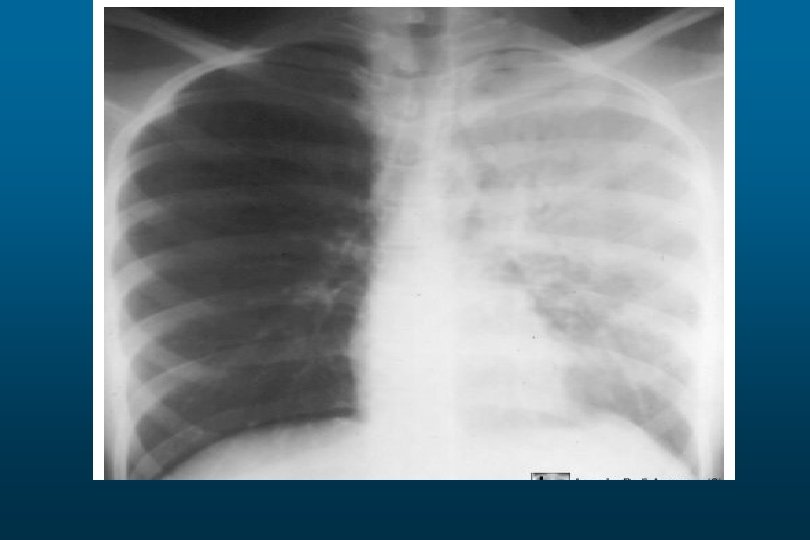

Right sided atelectasis

he right hemithorax is opaque There is a shift of the heart and trachea

he right hemithorax is opaque There is a shift of the heart and trachea away from the side ofo pacification This is characteristic of apleural effusion